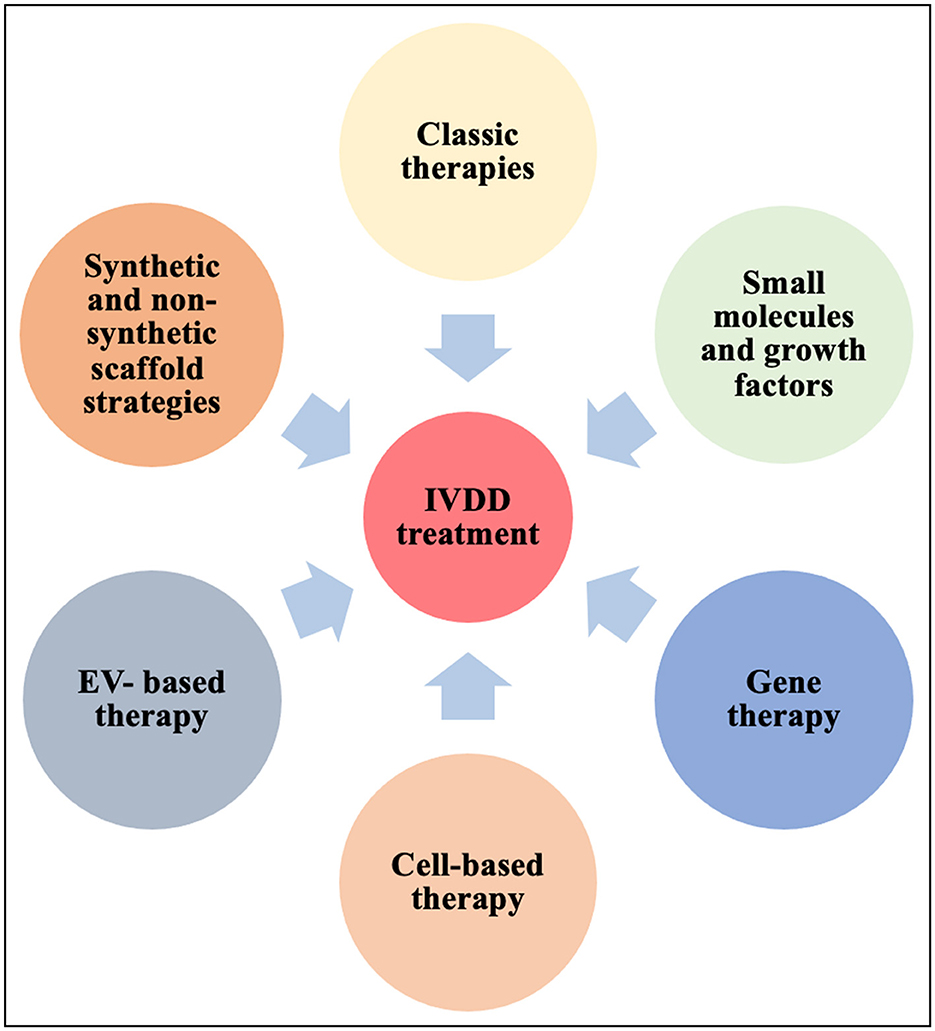

。Frontiers | Intervertebral disc degeneration—Current。[A01151548]動画で見る音声障害 Ver.1 [DVD] (1) 日本音声言語医学会。[A01371176]リウマチ生活指導 (リウマチのリハビリテ-ション (第1集)) 椎野 泰明。[A01206585]泌尿器ケア 13年9月号 18ー9―泌尿器科領域のケア専門誌 泌尿器科術前・術後のケアマニュアル [単行本]。[A01438740]膠原病診療ノート―症例と文献の分析に基づく実戦的マニュアル 三森 明夫。Doctor Stories Dr.コトー診療所のモデル。[A11076679]消化器内視鏡 第24巻11号 20 これは役立つ十二指腸病変アトラス (消化器内視鏡2012年11月号) 消化器内視鏡編集委員会。[A01214448]救急医学 2012年 01月号 [雑誌]。[A11849401]非浸潤性乳管癌のすべて [単行本] 秋山 太。[A12284976]スラッター 小動物の外科手術(全2巻)